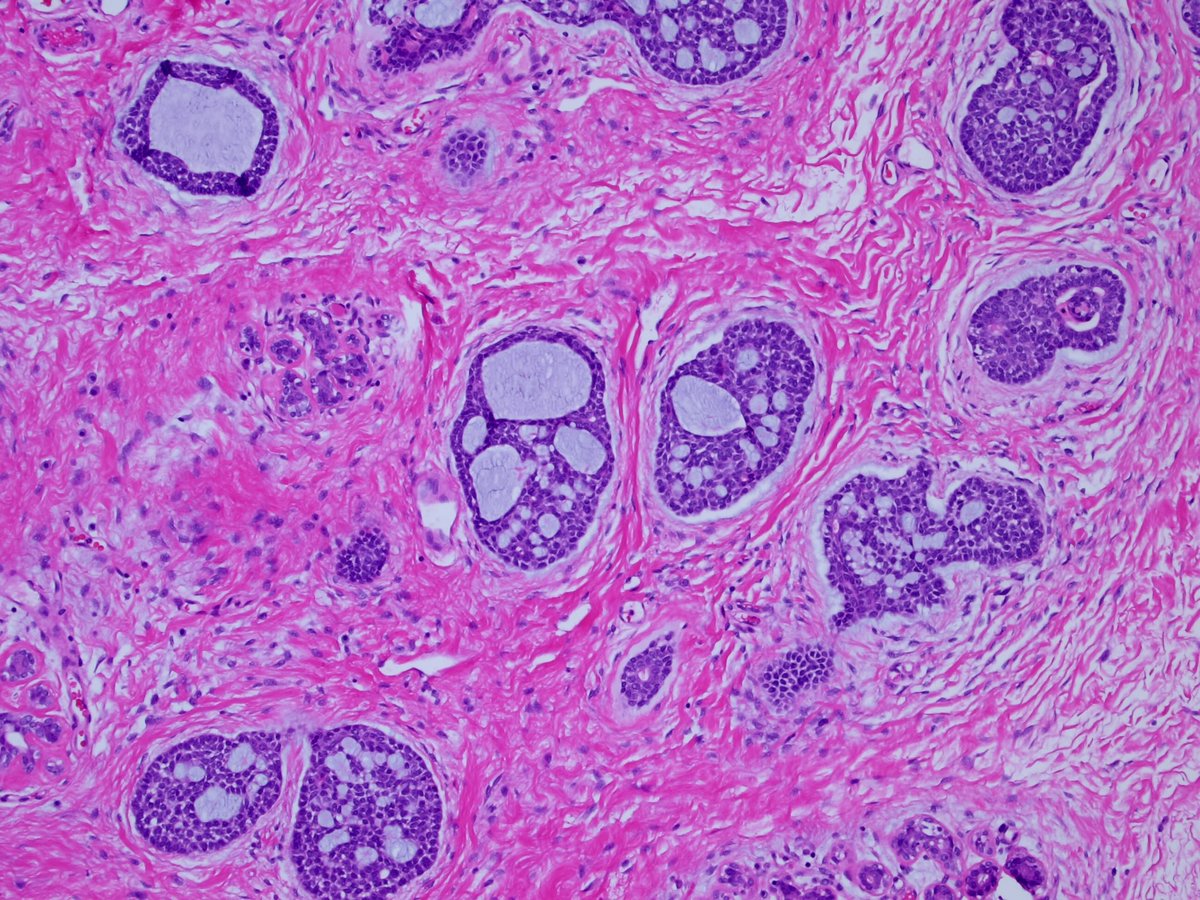

1. #Breastpath, with an #ENTpath flavor A case I had which pairs well with this sweet diagram by@TheKarenPinto (linked below) 40 year old woma